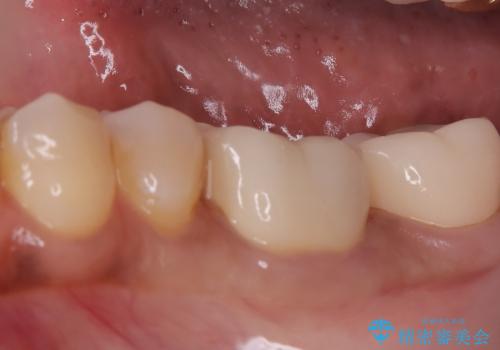

まず左下6番のヒビや弱くなった部分を除去し、セラミッククラウンが適切に装着できる形に整えました。隣接する7番についても同様に支台形成を行い、両方の歯を連続して補強する形としました。クラウンは、見た目の自然さと耐久性を兼ね備えたセラミックを選択し、咬合圧に配慮したデザインと高さ調整を丁寧に行いました。

また、ブラッシング時に不快感があった左下の親知らずは、炎症や清掃障害の原因になることから、治療前に抜歯しました。クラウン装着後は、違和感や痛みもなく、噛むときの安定感が向上。患者さんからは「しっかり噛めるようになって安心した」とご感想をいただきました。今後は定期的なメンテナンスで状態を保っていきます。